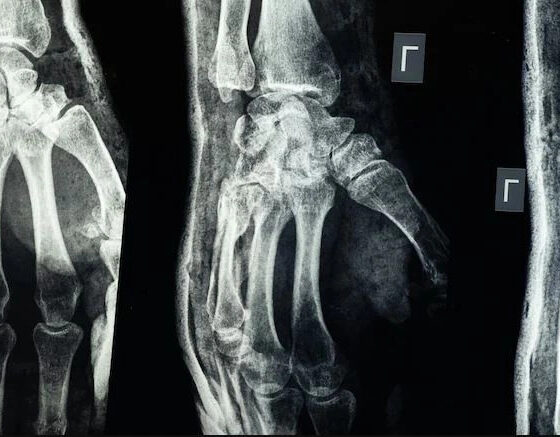

UBT NewsShkencëtarët kinezë kanë prezantuar një ngjitës të ri mjekësor të quajtur Bone-02, që riparon frakturat e eshtrave për vetëm tre minuta.

I frymëzuar nga guacat që ngjiten fort në sipërfaqe të lagështa, Bone-02 është i tretshëm nga trupi dhe zhduket brenda gjashtë muajve, duke shmangur nevojën për ndërhyrje të dytë kirurgjikale.

Ky ngjitës është testuar me sukses në mbi 150 pacientë, duke treguar forcë të madhe, ngjitje të shpejtë dhe tolerancë të lartë nga trupi.

Ai funksionon edhe në mjedise me shumë gjak dhe mund të zëvendësojë implantet tradicionale si vidat apo plakat metalike.

Bone-02 pritet të përshpejtojë shërimin, të ulë rrezikun e infeksioneve, dhe të ketë përdorim të gjerë në kirurgji, mjekësi emergjente, luftime apo katastrofa natyrore.

Ekspertët e quajnë një ndryshim të madh në trajtimin e frakturave. /A.Z/UBT News/